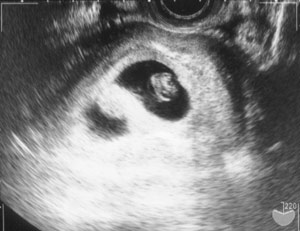

「あー、双子ちゃんだね。二卵性の」

「うん、生きてるよ〜。見た感じ、全然大丈夫〜v 二人とも、心拍確認できたし。今度来るのは2週間後でいいよv」

胎嚢の形がいびつだったのは、2つあったからで…え、だって、この前1つかなかったじゃん?

7週だよ。

別角度から。二人いると、両方を上手く写すのは難しいようだ。